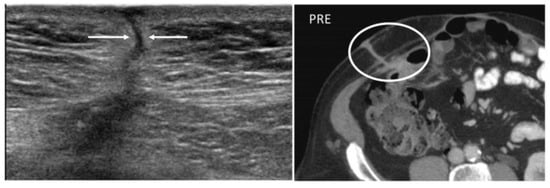

Figure 4. A 22-year-old man with reactivation of Crohn’s disease, presenting as a new enterocutaneous fistula. B-mode US with linear transducer (first picture) shows the presence of a fistulous trait between the skin and a superficial collection (arrows). Axial not-enhanced CT scan (second picture) revealed the course of the fistula, demonstrating communication between the bowel loops and the skin, together with a small collection (circle).

Enterocutaneous abdominal wall fistulae (ECFs) are abnormal connections between a bowel loop and the nearby skin that may be secondary to abdominal surgery or inflammatory bowel diseases. ECFs can either appear collapsed or patent with gaseous or fluid content (“tram-track” appearance) (Figure 4).

Abdominal wall fistulae are seen as hypoechoic or anechoic duct-like structures on US but are better studied on MR or CT, as these latter depict the connection between the bowel loops and the peritoneum or the cutis [16].

Fistulae need to be surgically repaired; otherwise, chronic infections may develop. Abscesses can indeed complicate ECFs: lesions above 2 cm, irregularly large, with thickened walls and patent peripheral sections should raise suspicion for superimposed abscesses [16].